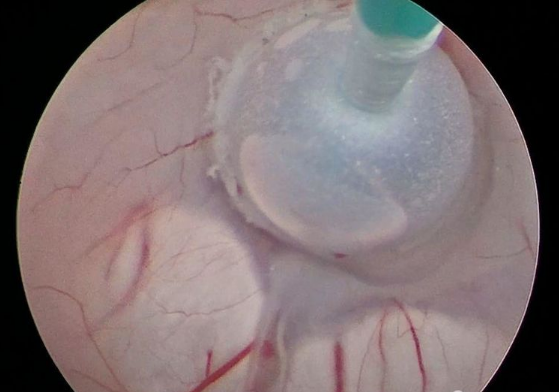

▲三脑室底造瘘术

在福建医科大学附属第一医院江常震教授的指导下,郭协力副院长、齐震主任、陈晓海副主任医师及蔡明发主治医师等人通力合作,于7月22日对王先生进行了微创神经内镜三脑室底造瘘术。手术利用脑室镜微创进入第三脑室,开放第三脑室底部约5mm,再造脑脊液循环通路,使脑室内积水得以流出。手术用时1个多小时就顺利完成,术后患者恢复到患病前状态,脑积水症状及影像均有不同程度的好转。